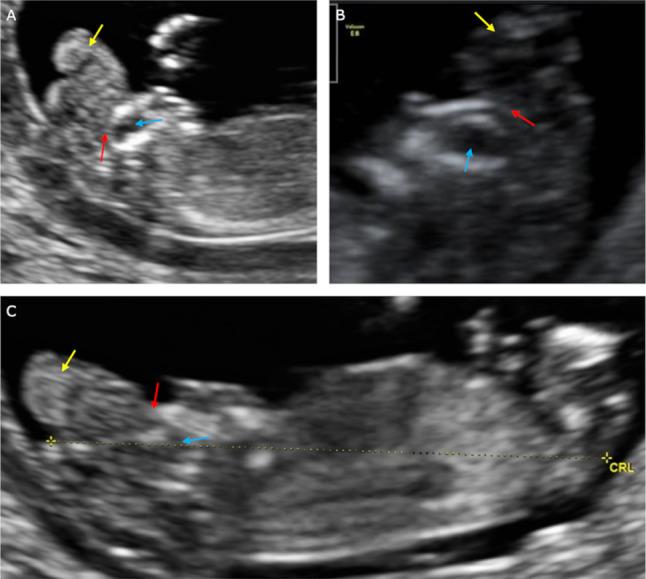

Analysis of the known prenatal ultrasonography (US) signs associated with AEAS. Simultaneously, the authors propose a new sign in the differentiation of acrania from exencephaly and anencephaly, called the "beret" sign.

In 10 cases, the absence of calvarium was diagnosed, allowing recognition of either AEAS stages or primary anencephaly. In 5 cases, cerebral structures were enclosed by an inertial rippled thin membrane, with a smooth outer contour. Between the described membrane and the brain structures, a thin anechoic space corresponding to cerebrospinal fluid was observed. This sign was defined as the "beret" sign. In these cases, acrania was diagnosed. In three cases calvarium was missing. The brain structures had an irregular appearance, did not wave and remained motionless. The outer contour was unequal as if divided into lobes. Amniotic fluid was anechoic. Exencephaly was diagnosed in these cases. In two cases calvarium, brain structures, and meninges were missing. The "frog eyes" sign and slightly echogenic amniotic fluid were visible. In this case, anencephaly was diagnosed.

分析与 AEAS 相关的已知产前超声(US)征象。同时,作者提出了一种新的征象,用于区分颅缝早闭和无脑畸形与无脑畸形,称为“贝雷帽”征象。

在 10 例病例中,诊断为颅骨缺失,能够识别 AEAS 阶段或原发性无脑畸形。在 5 例病例中,大脑结构被惯性波纹状薄膜包围,外轮廓光滑。在描述的膜和脑结构之间,观察到一个薄的无回声空间,对应于脑脊液。该征象定义为“贝雷帽”征象。在这些病例中,诊断为颅缝早闭。在 3 例病例中,颅骨缺失。脑结构外观不规则,无波动且保持静止。外轮廓不均匀,似乎分为叶。羊水呈无回声。在这些病例中,诊断为无脑畸形。在 2 例病例中,颅骨、脑结构和脑膜缺失。可见“青蛙眼”征和稍高回声羊水。在这种情况下,诊断为无脑畸形。